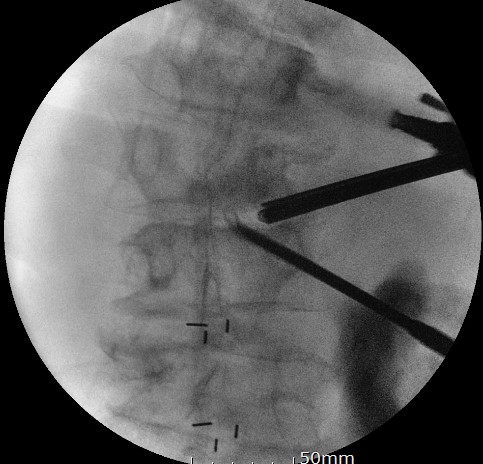

x-ray에서는

디스크 간극이 좁아져서

신경통로가 다 눌려보이는 환자분이셨습니다

측만증도 이에 더 심하게 악화되었습니다

CT를 보면

검게 보이는 병변은 디스크가 다 닳아서 없어진 것을 보실 수 있게 됩니다

양방향 척추 내시경을 통해

디스크 하나하나에

케이지를 삽입하여

추간공 간극을 벌리는 작업을 진행하였구요

내시경으로 감압과 동시에

추간공을 확공하니

신경통로에 대한 확보 및

측만증 정렬도 반듯하게

되는 수술을 진행하였습니다

수술을 마치고는

4마디에 대해서

최소침습 나사못 고정으로

마무리를 진행하였구요

수술 전에 비해

측만증도 해결이되고

추간공 감압술도 해결, 중심협착증도 정리가 된

결과를 볼 수 있게 되었습니다